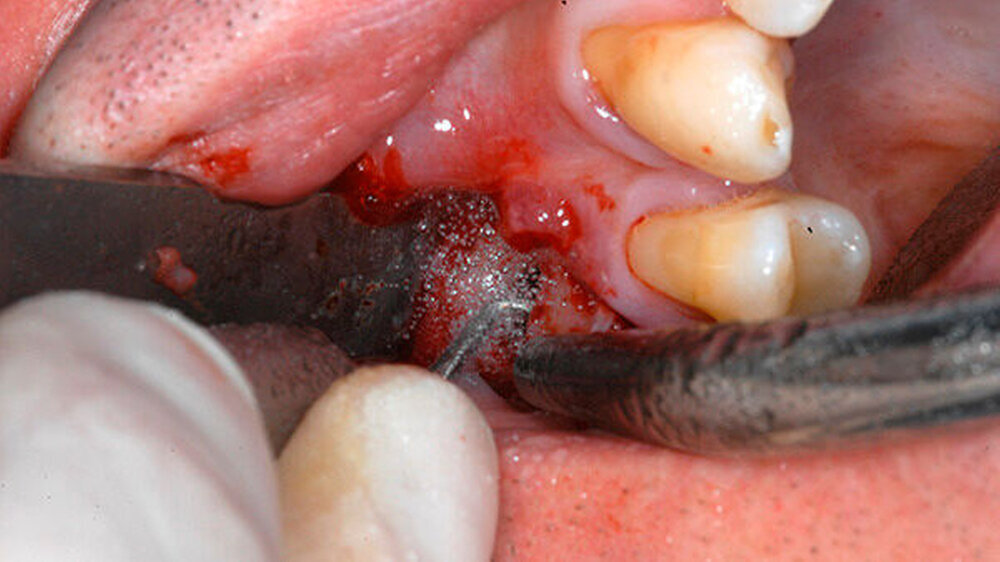

Mit einem ultraschallgetriebenen diamantierten, abgewinkelten Instrument wurden beide Wurzelkanäle der mesiobukkalen Wurzel von retrograd präpariert (Abbildung 3). Das frakturierte Instrument konnte so dargestellt (Abbildung 4) und entfernt werden.

Beide mesiobukkalen Wurzelkanäle wurden mit einem Ultraschallansatz etwa 3 mm tief von retrograd präpariert und gesäubert. Biodentine (Septodont) wurde als retrogrades Wurzelkanalfüllmaterial gewählt, nach Herstellerangaben angemischt und retrograd appliziert (Abbildung 5). Der mukogingivale Lappen wurde adaptiert und vernäht. Das postoperative Röntgenbild zeigte eine vollständige Entfernung des frakturierten Instruments sowie einen Knochendefekt um die mesiobukkale Wurzelspitze herum (Abbildung 6).